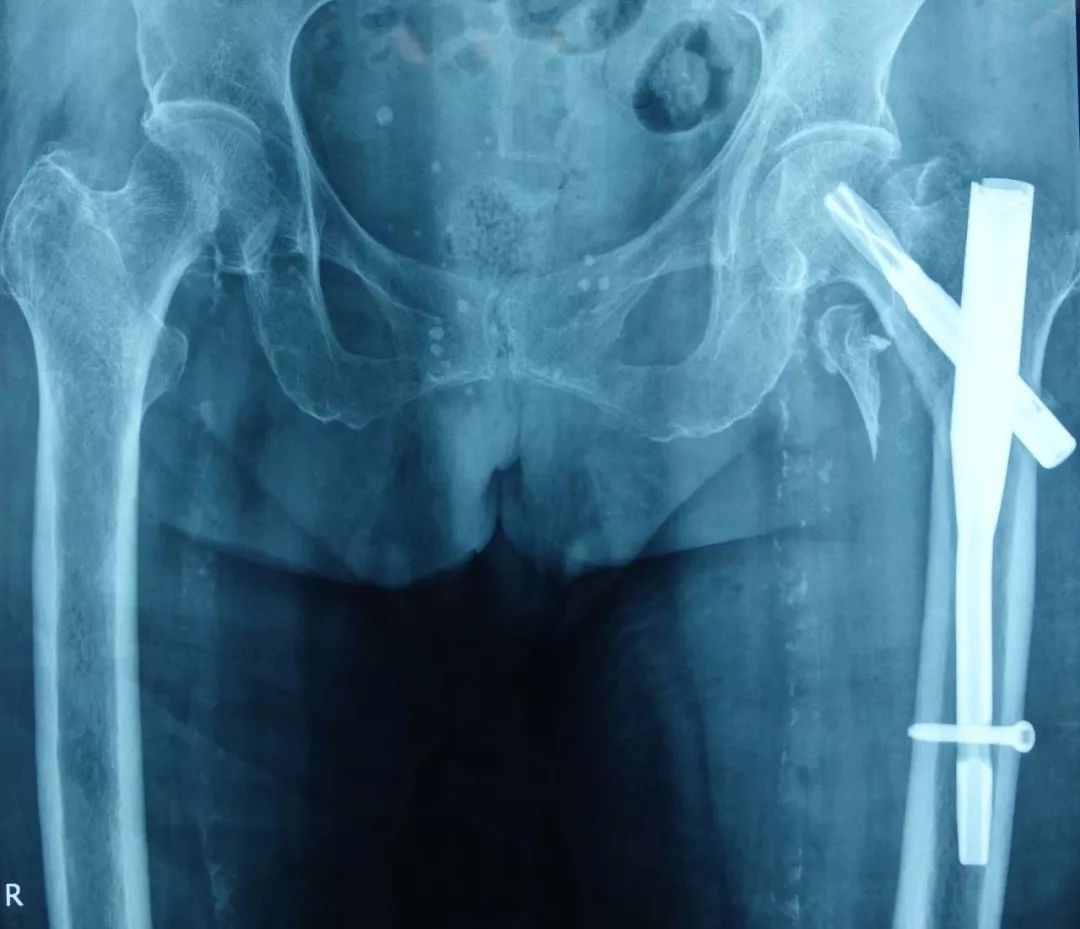

这是一个股骨粗隆间骨折的老年患者,和其他人一样,也是走路时不小心摔倒导致骨折,骨折移位明显,而且有较大的骨碎块。

外院医生给这位患者做了骨折内固定手术,可以看到骨折对位良好,骨碎块未作特殊处理。